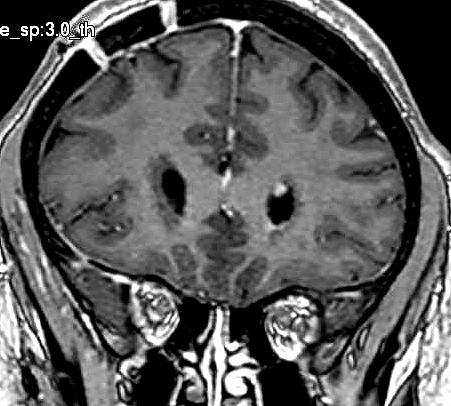

| Fem. 17a. |

| Nódulo sólido homogêneo preenchendo o III ventrículo, com limites precisos, com hipossinal em T1 e hipersinal em T2 e FLAIR, que se impregna por contraste paramagnético. Lesão menor implantada no assoalho do IV ventrículo provavelmente representa disseminação por via liquórica. |

| F. 17a. Tumor teratóide rabdóide atípico de III ventrículo. RM | HE | VIM, GFAP | HHF35, desmina, 1A4 | AE1AE3, EMA |